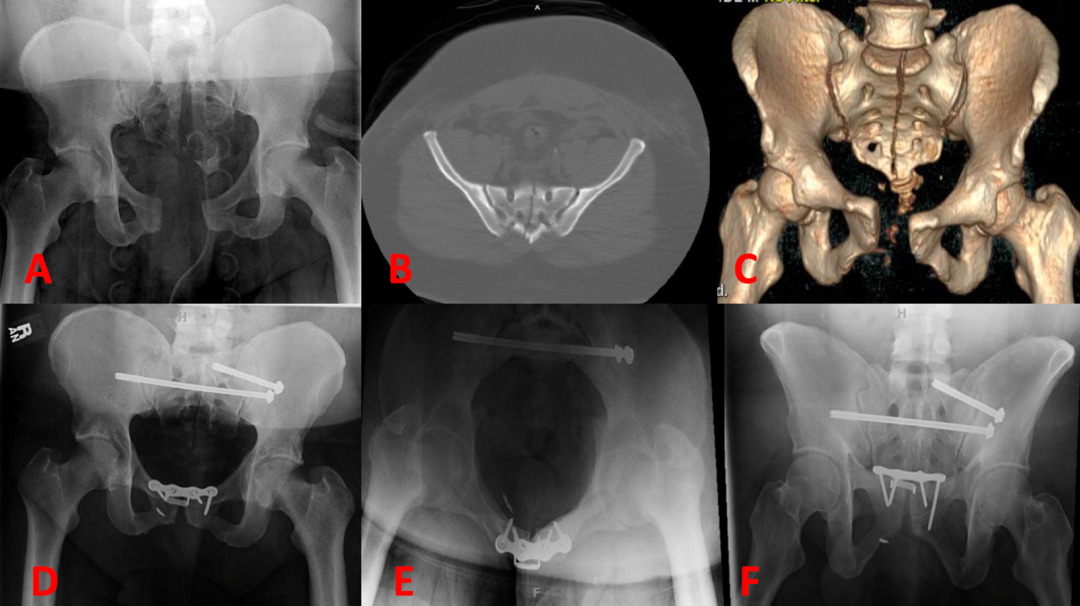

Midline Sacral Fractures Review of the Literature Published in Spartan Medical Research Journal

Unstable Pelvic Ring Fractures Maimonides Emergency Medicine Residency

Sacral Fracture OrthoFixar 2024